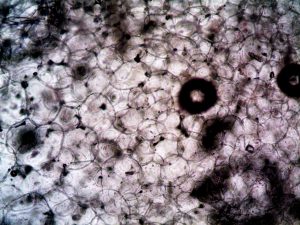

אילו ממצאים בבדיקות דם צריכים להדליק חשד ללוקמיה?

לוקמיה מתגלה פעמים רבות כבר בבדיקות דם שגרתיות.

רופא סביר חייב להתייחס לממצאים חריגים ולא להסתפק בפרשנות כללית.

- עלייה או ירידה חריגה בתאי דם לבנים

- אנמיה שאינה מוסברת

- ירידה בטסיות

- שילוב של מספר ערכים לא תקינים

התעלמות מממצאים כאלה או אי הפניה לבירור נוסף עלולים להיחשב רשלנות.